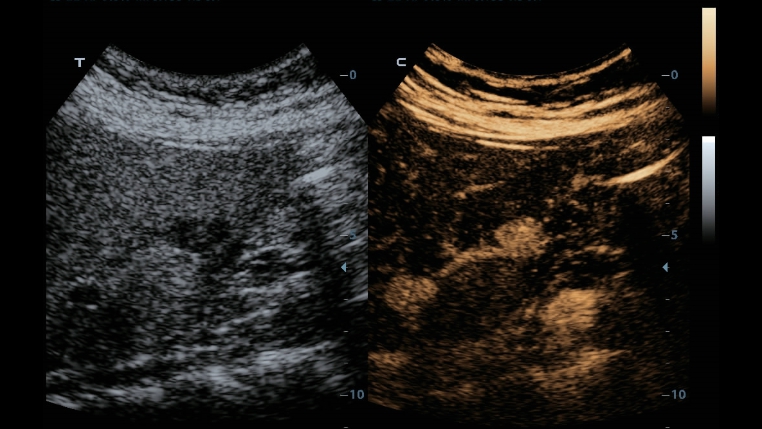

G?owice ComboWave

W porównaniu z tradycyjnymi g?owicami, w g?owicach ComboWave zastosowano nowy typ kompozytowego materia?u piezoelektrycznego, aby uzyska? znacz?c? optymalizacj? spektrum akustycznego i zredukowa? impedancj? akustyczn?. W po??czeniu z unikaln? technologi? 3T Mindray, g?owice liniowe ComboWave pozwol? uzyska? wysokiej jako?ci obrazowanie o doskona?ej rozdzielczo?ci i jednorodno?ci w badaniach tarczycy, piersi, naczyń krwiono?nych i innych.